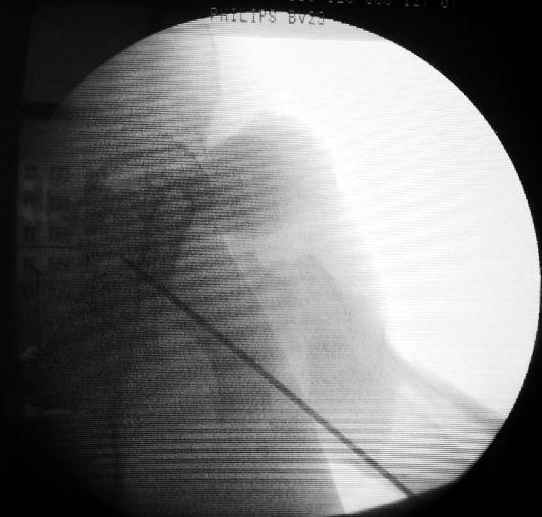

Как раз недавно у меня был примерный случай: больному 36 лет, поступил ночью, травма в результате мотоциклетной аварии, кроме чрезвертельного и спирального перелома левого бедра имеется переломы костей предплечья с этой же стороны. Скелетное вытяжение, а на следующий день больной про оперирован на ортопедическом столе с дистракцией. Чтобы не расколоть чрезвертельный перелом провели временную спицу ближе к переднему кортексу, из малого разреза костодержатель для репозиции, а фиксацию провели антиградным штифтом. Этапы операции на снимках.

Да, сейчас это и у нас самый напрашивающийся выбор. Сделали гвоздем ChM, картинки в приложении.